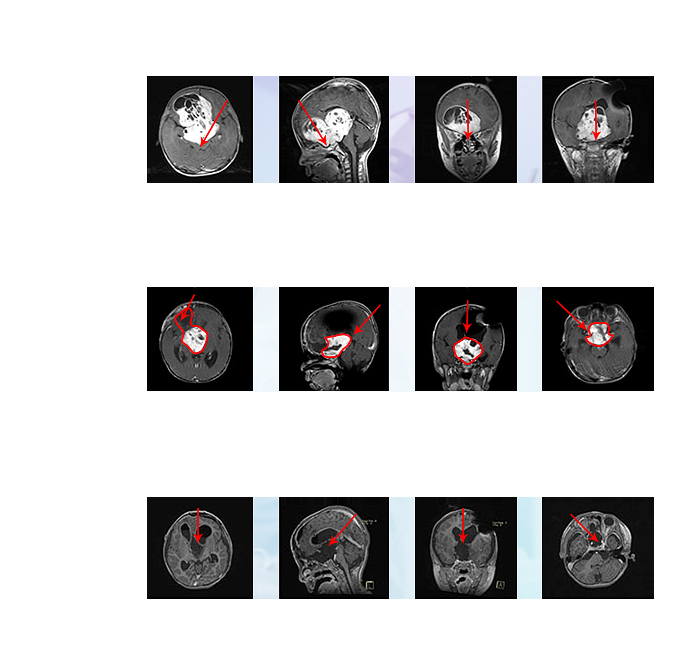

好奇、天真、充满星光,眼睛,是孩子探索国际的通路。不幸罹患视路胶质瘤,在局限的脑子里竟有着苹果大的较大肿瘤,造成患儿视力逐渐下降,初期在...